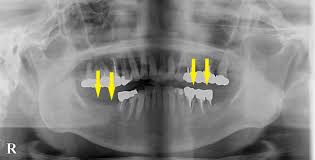

- 치아 상태: 부분 무치악(치아 일부 상실) 상태여야 하며, 완전 무치악(모든 치아가 없음)인 경우 지원 대상에서 제외됩니다.

- 지원 개수 제한: 평생 최대 2개의 치아에 한해 지원됩니다.